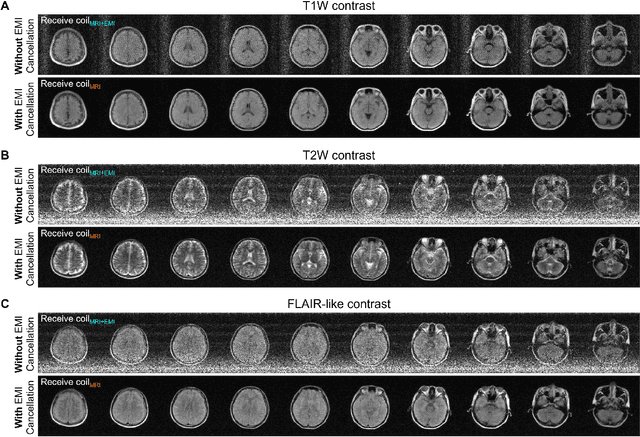

Abstract:At present, MRI scans are performed inside a fully-enclosed RF shielding room, posing stringent installation requirement and unnecessary patient discomfort. We aim to develop an electromagnetic interference (EMI) cancellation strategy for MRI with no or incomplete RF shielding. In this study, a simultaneous sensing and deep learning driven EMI cancellation strategy is presented to model, predict and remove EMI signals from acquired MRI signals. Specifically, during each MRI scan, separate EMI sensing coils placed in various spatial locations are utilized to simultaneously sample environmental and internal EMI signals within two windows (for both conventional MRI signal acquisition and EMI characterization acquisition). Then a CNN model is trained using the EMI characterization data to relate EMI signals detected by EMI sensing coils to EMI signals in MRI receive coil. This model is utilized to retrospectively predict and remove EMI signals components detected by MRI receive coil during the MRI signal acquisition window. We implemented and demonstrated this strategy for various EMI sources on a mobile ultra-low-field 0.055 T permanent magnet MRI scanner and a 1.5 T superconducting magnet MRI scanner with no or incomplete RF shielding. Our experimental results demonstrate that the method is highly effective and robust in predicting and removing various EMI sources from both external environments and internal scanner electronics at both 0.055 T (2.3 MHz) and 1.5 T (64 MHz), producing final image signal-to-noise ratios that are comparable to those obtained using a fully enclosed RF shielding. Our proposed strategy enables MRI operation with no or incomplete RF shielding, alleviating MRI installation and operational requirements. It is also potentially applicable to other scenarios of accurate RF signal detection or discrimination in presence of external and internal EMI or RF sources.